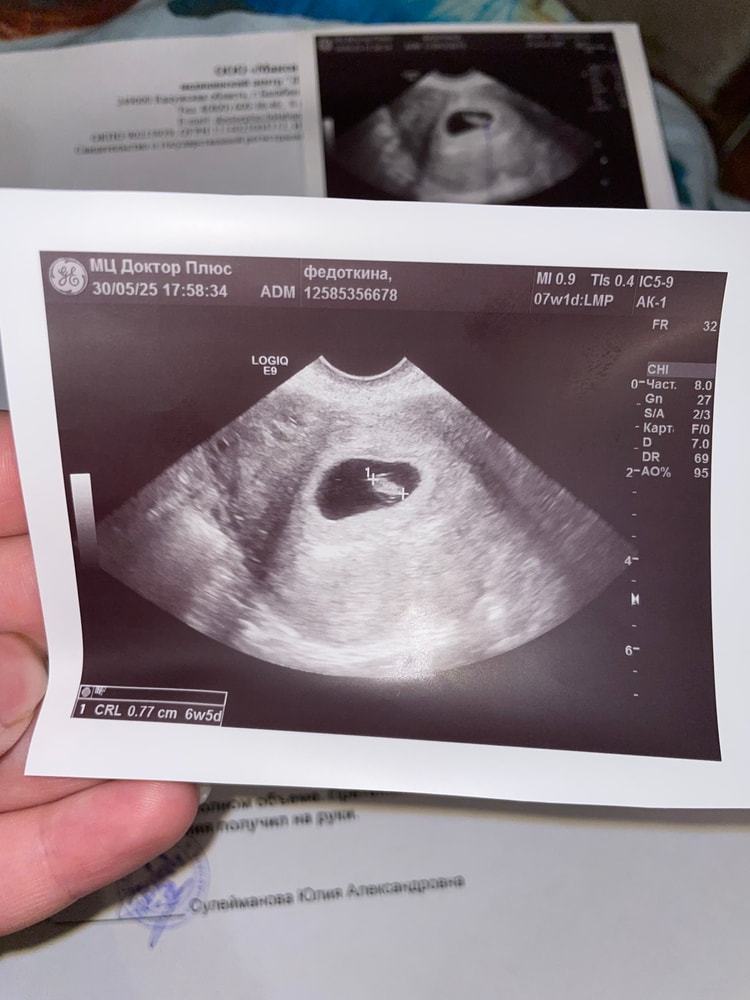

Привет малыш 🥹💕